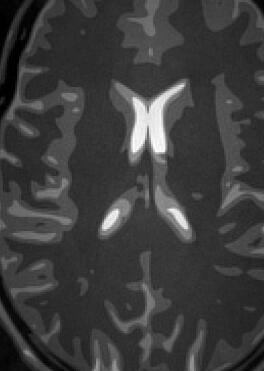

The simulation employs a realistic analytical MRI brain phantom [50], of dimensions , i.e., .

Fig. 14 exhibits the reconstruction results with the spiral trajectory with for . The reconstructed images are displayed alongside profile plots of row . The same is also presented in Figures 13 for .